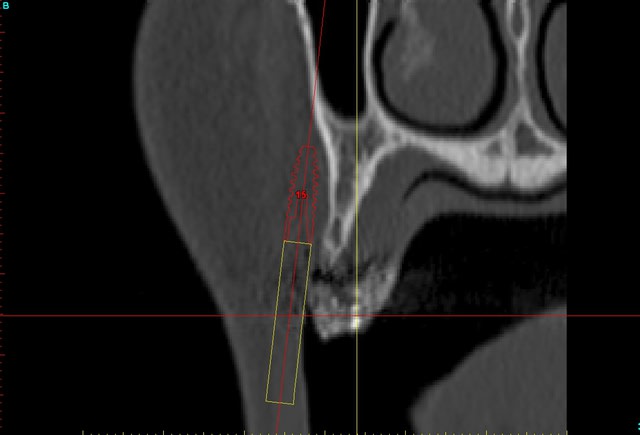

un autre exemple pour montrer que la visualisation est très correcte dans la technique en envellope:

--